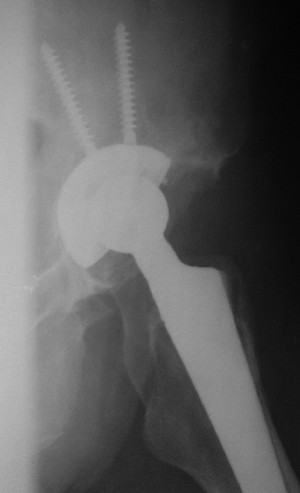

После протезирования прямой 5/04/04

Больной 18 мая 2003 года в автоаварии получил перелом левой вертлужной впадины, вывих бедра. Госпитализирован в один из стационаров области.Вывих вправлен. В последствии бедро вывихивалось еще дважды. На консультацию был представлен снимок от 19.05.03г., больной переведен к нам 3.06.03г. Снимок при поступлении - перелом впадины, задне-верхний вывих бедра. 05.06.2003 г. выполнено открытое вправление вывиха левого бедра и остеосинтез стенки вертлужной впадины двумя винтами. Послеоперационный период без осложнений. Объем движений в левом тазобедренном суставе восстановился полностью. Выписан на амбулаторное лечение в удовлетворительном состоянии с рекомендациями 3 месяца ходить на костылях без нагрузки на оперированную конечность. На контрольных рентгенограммах левого тазобедренного сустава 13.10.2003 г. - признаки консолидации перелома; плотность, форма головки и состояние суставных поверхностей удовлетворительные. Разрешена дозированная осевая нагрузка, на конечность с использованием дополнительной опоры. 19.12.2003 г. больной обратился с жалобами на боли в левом тазобедренном суставе. На рентгенограммах левого тазобедренного сустава 19.12.2003 г., 20.02.04г. - асептичекий некроз головки бедра. 5.04.04г. - эндопротез. Сейчас ходит без трости, не хромает. Особенность эндопротезирования - при удалении винтов прослежена линия перелома заднего края впадины и предложено установить чашку несколько меньшего диаметра, чтобы она была покрыта несломанной частью.